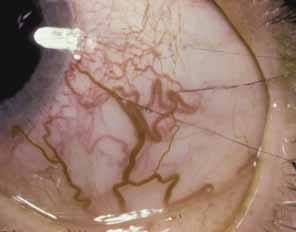

ANIRIDIA Aniridia is a bilateral congenital anomaly in which the iris is markedly underdeveloped (see Fig. 5). The term aniridia is a misnomer because there is generally a rudimentary iris stump of variable extent visible on examination of the angle. Two thirds of cases are autosomal dominant with a high degree of penetrance. This form has been linked to a mutation on the short arm of chromosome 11 (PAX6 gene).28 The remainder are sporadic, and approximately 20% are associated with Wilms' tumor.29 However, only 1% of patients with Wilms' tumor have aniridia. A deletion of the short arm of chromosomes 11 and 13 has been demonstrated in the association of Wilms' tumor and sporadic aniridia.30,31 Associated ocular conditions include keratopathy, cataract, ectopia lentis, foveal hypoplasia, and optic nerve hypoplasia. Optic nerve hypoplasia occurs in 75% of aniridic patients and may be related to poor macular development.32 Photophobia, nystagmus, decreased vision, and strabismus are common manifestations in aniridia. The visual acuity is generally no better than 20/200 because of the foveal hypoplasia and the accompanying nystagmus. Progressive corneal opacification and pannus are commonly seen. These occur circumferentially in the periphery and extend centrally over time. In rare cases they may completely opacify the cornea. Cataracts occur in 50% to 85% of patients.33 These cataracts may progress and require surgical removal by the second or third decade of life. In addition, the lens may be displaced with a segmental absence of zonules. In most cases of glaucoma associated with aniridia, the glaucoma does not develop until later in childhood or in early adulthood.33 Therefore, the clinical signs such as buphthalmos, megalocornea, and tears of Descemet's membrane are rare. The glaucoma may be the result of trabeculodysgenesis or to progressive closure of the trabecular meshwork by the residual iris stump.34 If glaucoma develops during infancy, a goniotomy or trabeculotomy may be indicated. It has been suggested that early goniotomy may prevent the progressive adherence of the residual peripheral iris to the trabecular meshwork.35 In older children, medical therapy to control intraocular pressure should be attempted first. Any form of surgery has the risk of injuring the unprotected lens and zonules, and filtering procedures have an increased risk of vitreous incarceration. Cyclodestructive procedures may be necessary in certain patients with uncontrolled advanced glaucoma. STURGE-WEBER SYNDROME (ENCEPHALOTRIGEMINAL ANGIOMATOSIS) In Sturge-Weber syndrome (Figs. 13 and 14), the facial hemangioma follows the distribution of the trigeminal nerve. The facial hemangioma is usually unilateral but may be bilateral. Facial hemihypertrophy is commonly seen in the area of involvement. An ipsilateral leptomeningeal hemangioma may produce a seizure disorder. Conjunctival, episcleral, and choroidal hemangiomas are also common abnormalities. Diffuse uveal involvement has been termed the “tomato-catsup” fundus.36 No clear hereditary pattern has been established.

Glaucoma more often occurs when the ipsilateral facial hemangioma involves the lids and conjunctiva (Fig. 15). Glaucoma may occur in infancy, late childhood, or young adulthood. The glaucoma that occurs in infancy looks and behaves similar to glaucoma associated with isolated trabeculodysgenesis and responds well to goniotomy. The glaucoma that appears later in life is probably related to elevated episcleral venous pressure from arteriovenous fistulas.37 In older children, medical therapy should be attempted first. However, if this is not successful, trabeculotomy or trabeculectomy should be considered.